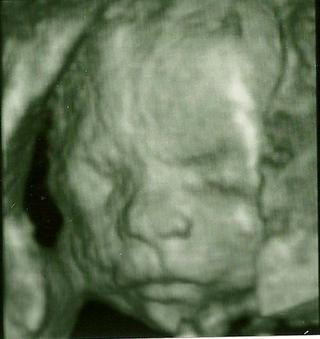

Baby ktore ste uz mali sono, kolko teraz uz meria babatko?

@23lenka - ano chceme aj na 3D - tak do mesiaca. zajtra sa chcem objednat. cena tusim zacina od £90, ale to je len za fotky a potom sa to splha az do vyse 200 - podla toho co si chces odniest. my chceme len zopar fotiek a dvd, tak asi okolo £150. je to dost, ale pri prvom som nebola a teraz si to dame 'pod stromcek'. 🙂

u nas v Kosiciach v Procare nemocnici pytaju za 4D ultrazvuk + DVD k tomu 55 Eur.

@smajka no je to dost nie ....aj u nas stoji 195£...a to je k tomu 15min dvd aj s hudbou 10 foto vo formate A5....a to vsetko je 195£ oni uz nevedia kolko za to pytat...a keby som bola bola na tej klinike zaregistrovana mam to vsetko za 100£ pekne nie?My este s mojim rozmyslame ci ist ci ee....no a dufam ze potom das nejake fotecky....a tam ti aj pohlavie povedia to bude super nie?